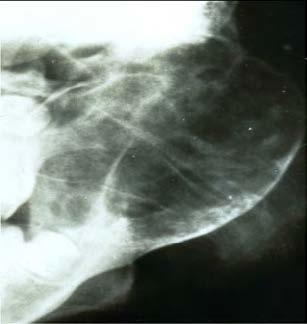

Radiographically

■ a radiolucency which can be either unilocular or multilocular in appearance

■ Borders are variable, often irregular in shape and may be ill-defined (again, giving the suggestion of malignancy)

■ Teeth may be displaced

■ we may see cortical expansion and thinning ~ the cortex itself can become quite thin

What does this person have?

This is a Aneurysmal Bone Cysts